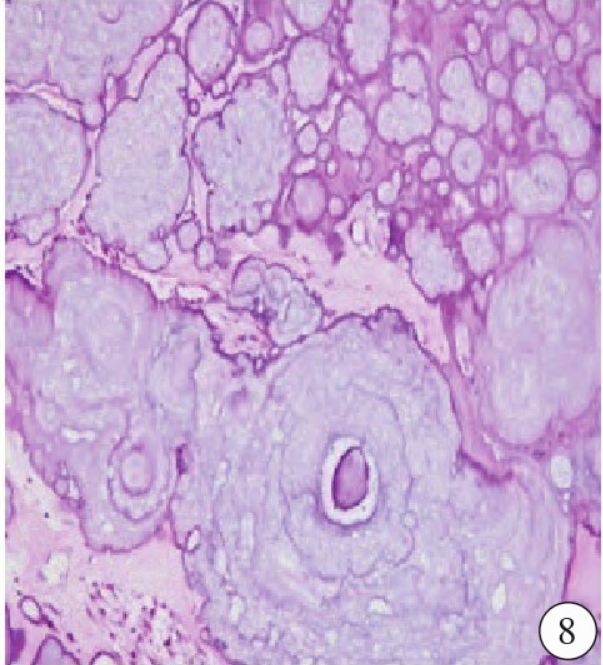

手术及病理:左侧额部硬膜张力稍高,额叶皮质表面见3.0 cm囊性病灶,病灶深居额叶白质内向脑室方向发展,囊性病灶内无确切“囊壁”膜型结构,囊液呈草黄色,其内多处钙化灶,病灶无明显包膜,仅与同侧侧脑室额角处有菲薄膜型结构相隔,病灶探查至清晰显露室间孔,脑室内光滑无病变。大体观察:囊肿界限清楚、呈单房样,其内见半透明胶冻样物质。病理镜下见囊壁被覆单层柱状细胞,部分上皮见纤毛或黏液(图8)。病理诊断:侧脑室旁神经胶质囊肿。

图8 病理镜下见囊壁被覆单层柱状细胞,部分上皮见纤毛或黏液。